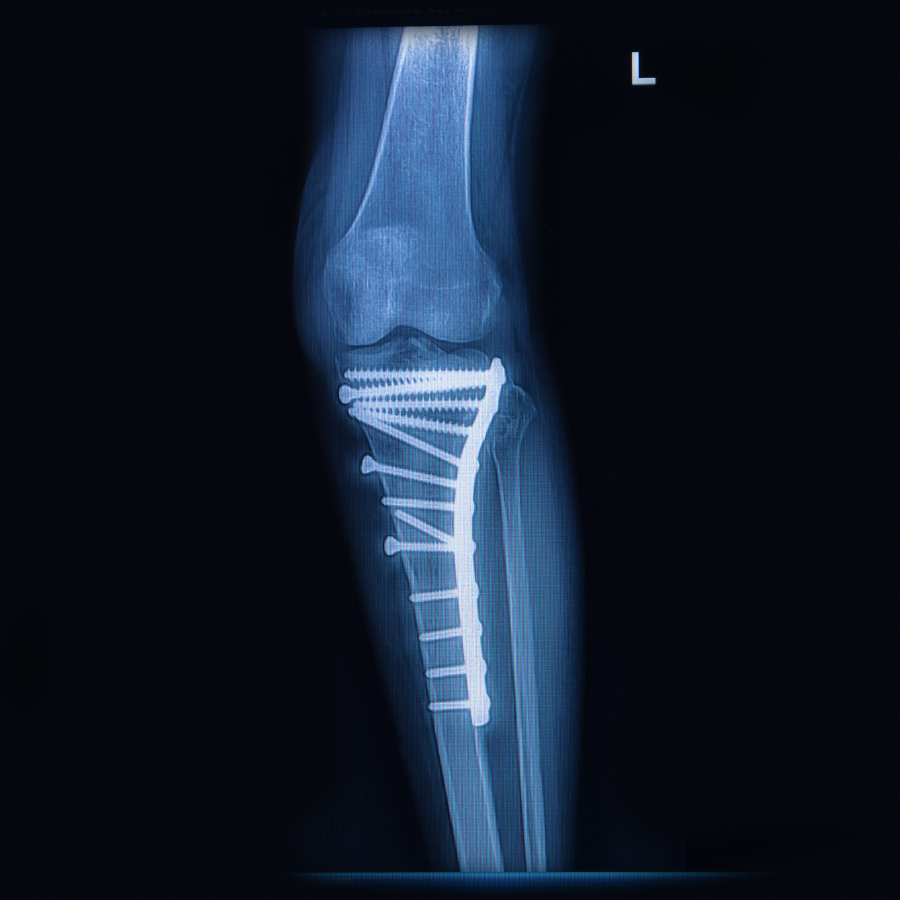

Verwijderen van pennen of schroeven

Tijdens de operatie worden botfragmenten gefixeerd met pennen en schroeven. Het bot herstelt en wordt weer belastbaar. Bij voorkeur wordt het osteosynthese materiaal niet verwijderd, tenzij je er klachten van ervaart. In dat geval kunnen de pennen of schroeven tegen zachtere weefsels zoals spieren, pezen en bindweefsel drukken. Als dit het geval is, kan er een tweede operatie nodig zijn om de pennen en schroeven te verwijderen. Verder kan je daar niets aan doen.

Gelukkig is het verwijderen van osteosynthesemateriaal vaak een kleine operatie met korte hersteltijd.